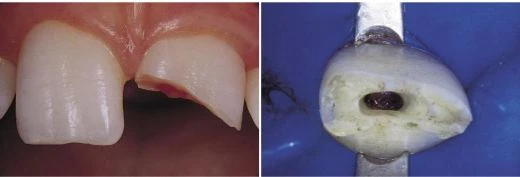

Có 2 tình huống buộc phải liên quan đến rìa cắn là: mòn răng và vỡ răng. Răng càng mòn chừng nào thì rìa cắn càng liên quan đến xoang tủy chừng đó. Đối với răng mòn hoặc răng gãy ở 1/3 giữa thân răng thì việc mở xoang tủy hoàn toàn trên rìa cắn (hình 11.34 và 10.25).

Hình 11.34. A. Răng #21 chấn thương gãy ở 1/3 giữa thân răng, ảnh hưởng tới tủy. B. Trong trường hợp này, xoang tủy được mở từ mặt nhai.

Hình 10.25. A. Răng bị gãy cần điều trị nội nha, tuy nhiên răng vẫn chưa mọc lên hoàn toàn. Để đặt móc giữ đê, cần tạo hai nút composite ở mặt trong và ngoài của răng. B. Xoang tủy được tạo trên bờ gãy của răng.